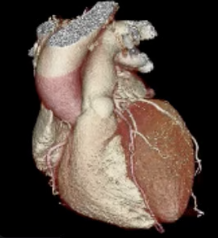

Cardiac CT

A cardiac CT scan is a non-invasive imaging test that uses X-rays to create detailed 3D pictures of the heart and blood vessels. It helps doctors detect coronary artery disease, calcium buildup, structural heart problems, or congenital abnormalities.